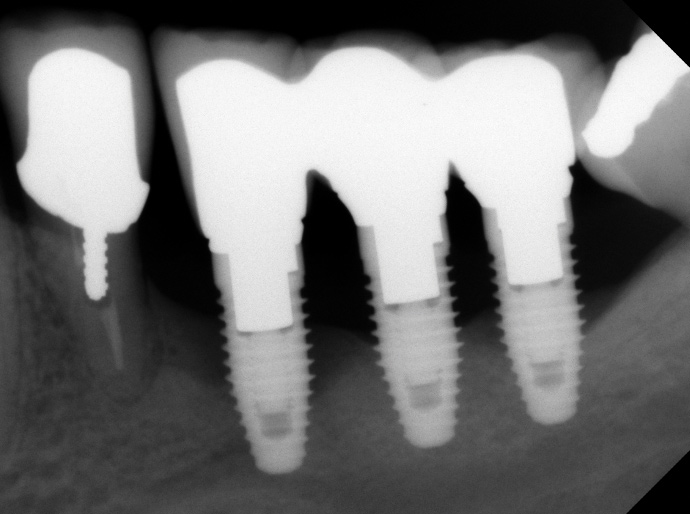

Fig 7. Radiographic image of the area suggesting severe bone loss around the dental implants.

Figure 7

Fig 5. Clinical view of implants depicting suggested bone loss. Plaque was present throughout, and the distal-most implant had substantial purulent exudate.

Figure 5

Fig 6. From a more anterior view, it was apparent that the labial positioning of these implants was outside the alveolar housing.

Figure 6

Studies have demonstrated that much like teeth, dental implants have a certain biologic dimension established following their healing after surgery and much of this understanding comes from evidence obtained from animal studies.18,19 However, in a seminal article on implant placement, Salama et al20 further highlighted the concept of bone surrounding an implant. A violation to the dimension of bone present in any of the buccal-palatal, mesial-distal, or apical-coronal directions will lead to bone loss (Figure 5 through Figure 7). This relates to the blood supply necessary to maintain the bone surrounding a dental implant. If an implant is placed in a position in which the minimal bone dimensions are not respected, crestal loss can be anticipated. While this may represent a contained lesion and remain static, it may not always be the case. In implants designed with a surface roughened to the top, suboptimal plaque control can lead to ongoing bone loss, because the exposed roughened surface is challenging to clean and will act as a plaque-retentive feature.21